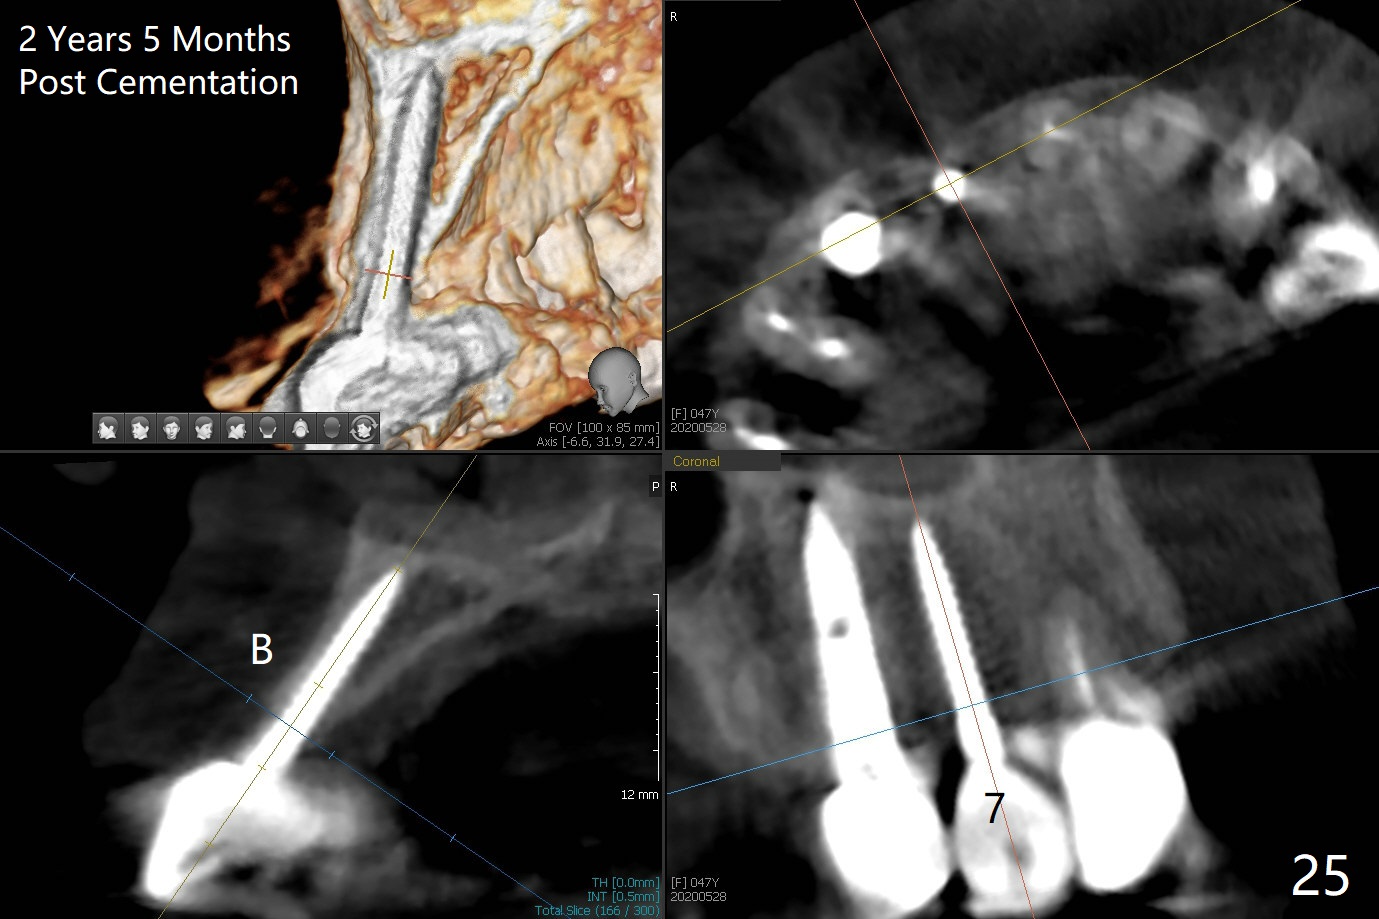

Since the ridge at #7 is ~ 4 mm, a 2.5x14 mm 1-piece implant is placed (Fig.8) after 1.2 mm (Fig.7), and 1.5 mm drills at 12 mm and 2 mm drill at 8 mm. Later the implant is placed deeper (Fig.10). There is no bone loss 7 or 12 months postop, respectively (Fig.11,12). After Diode gingivectomy, there is papillary formation (Fig.13). No provisional is provided after impression (with the abutment torqued at #6) for oral hygiene. With access holes at #6 and 7, crowns are bonded with minimal residual cement (Fig.14 <, which is removed later). There is no hard (Fig.15,16) or soft (Fig.17 *) atrophy 26 months postop, i.e., 13 months post cementation, due to the presence of socket shield (Fig.15 <, as compared to Fig.1). In fact the tooth #8 has mobility and fremitus (short root/poor crown/root ratio, Fig.16); occlusal adjustment is done 13 months post cementation. The crown is dislodged 2 years 1 month post cementation; a prefabricated post is being tried in (Fig.18). There is no atrophy, bone loss or infection at #6 (with socket sheath (*)) or 7 two years 5 months post cementation (Fig.20-27).